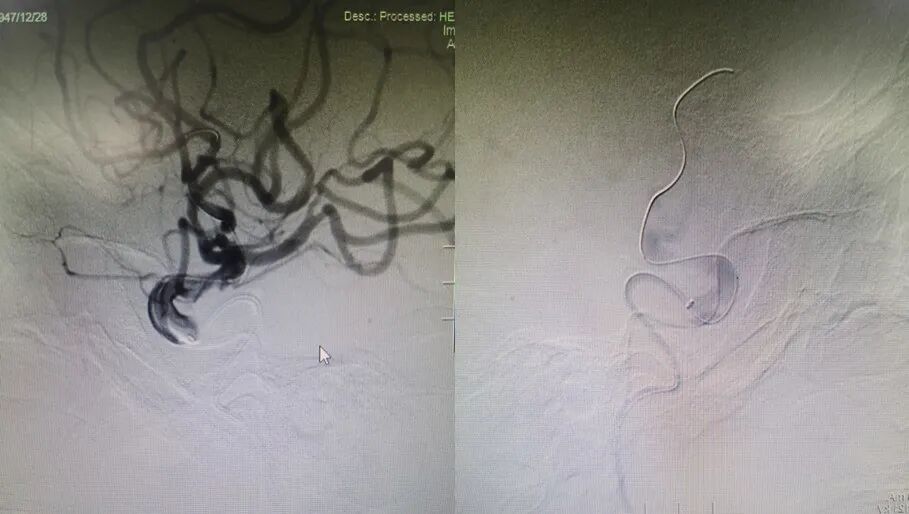

治疗过程

于左侧锁骨下动脉。

导丝怎么扩【载药时代 球扩天下】NOVA DES®颅内药物洗脱支架在症状性颅内动脉狭窄中的应用—烟台鲁东医院使用体会二例!_https://www.jmylbn.com_新闻资讯_第7张

微导丝置于大脑后动脉远端,造影显示左侧V4段重度狭窄,前向血流显著延迟。

导丝怎么扩【载药时代 球扩天下】NOVA DES®颅内药物洗脱支架在症状性颅内动脉狭窄中的应用—烟台鲁东医院使用体会二例!_https://www.jmylbn.com_新闻资讯_第8张

球囊通过病变,定位准确后扩张,压力8atm,维持30S。

导丝怎么扩【载药时代 球扩天下】NOVA DES®颅内药物洗脱支架在症状性颅内动脉狭窄中的应用—烟台鲁东医院使用体会二例!_https://www.jmylbn.com_新闻资讯_第9张

置入赛诺神畅 NOVA DES®内药物洗脱支架2.5*12mm,压力12atm,维持30S。

导丝怎么扩【载药时代 球扩天下】NOVA DES®颅内药物洗脱支架在症状性颅内动脉狭窄中的应用—烟台鲁东医院使用体会二例!_https://www.jmylbn.com_新闻资讯_第10张